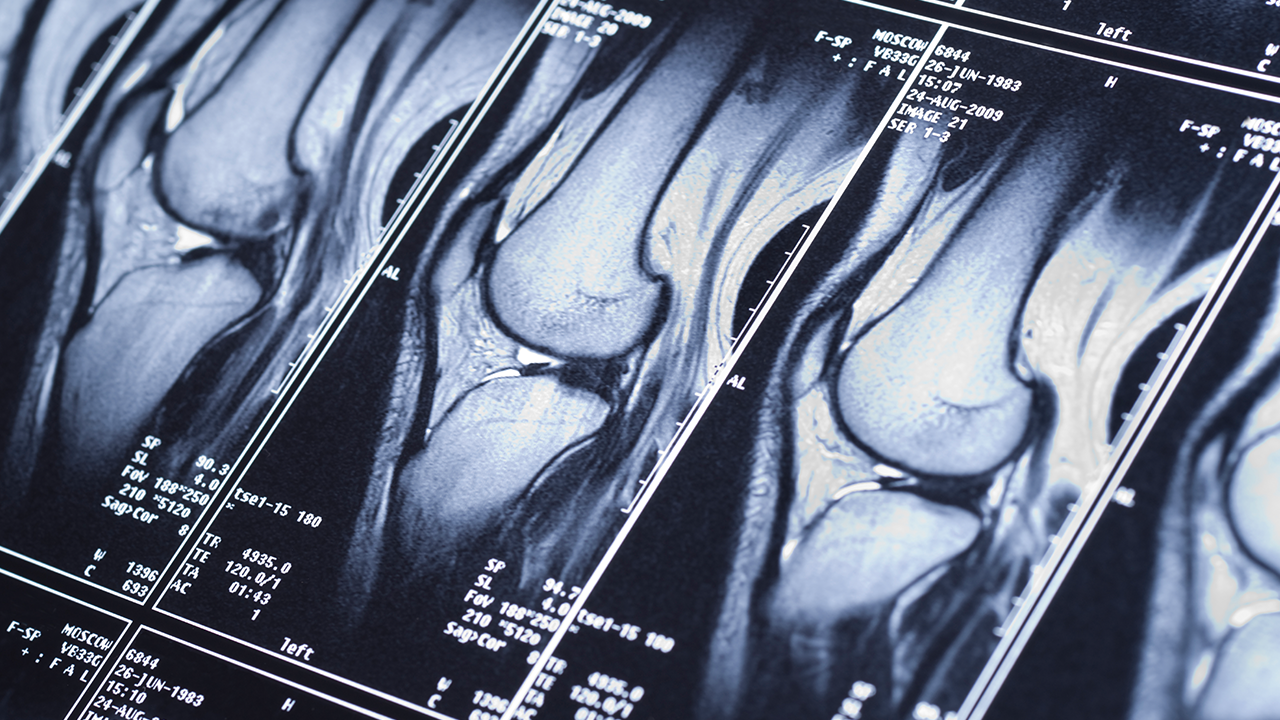

Our musculoskeletal radiology program collaborates closely with the sports medicine team at UC Health. Fellowship-trained radiologists, specialized imaging and shared expertise support athletes and active individuals in diagnosis, treatment and recovery. Our team’s approach aims for faster healing and safe return to activity.

At UC Health, fellowship-trained radiologists work side by side with specialists to deliver expert imaging, diagnosis and treatment—backed by research and commitment to your well-being.

Subspecialty-trained musculoskeletal radiologists on staff